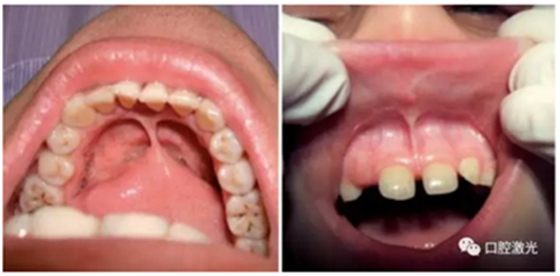

半导体激光进行系带整形术

口腔系带整形是口腔外科手术中较为常见的手术,一般包括对唇系带和舌系带的延长、整形。其中,唇系带整形通常在口腔正畸中有广泛的应用。半导体口腔激光拥有便携性强、结构紧凑、效率高等特点,能有效杀灭口腔细菌和对血液、软组织起到凝固的作用。半导体口腔激光的波长通常是810nm至980nm,可以使用连续模式或者脉冲模式,采用接触或非接触的治疗手柄。

利用口腔激光进行系带整形需要实施局麻,可以使用2%利多卡因。采用300um激光光纤,设置功率为4W。激光光纤垂直和水平作用于系带上,从而使系带黏膜得到很好的分离。通过这种方式,系带在水平方向上可以很容易获得一个较深的切口。系带整形后的伤口是呈菱形,整个过程大约4,5分钟。在任何情况下,都不需使用缝针。可以使用冰敷的方式降低组织温度,控制组织坏死的风险。术后复检的时间为1周、3周和3个月。复检时,包括疼痛,出血,水肿,疤痕组织形成以及伤口愈合的特征都应得到有效的评估。